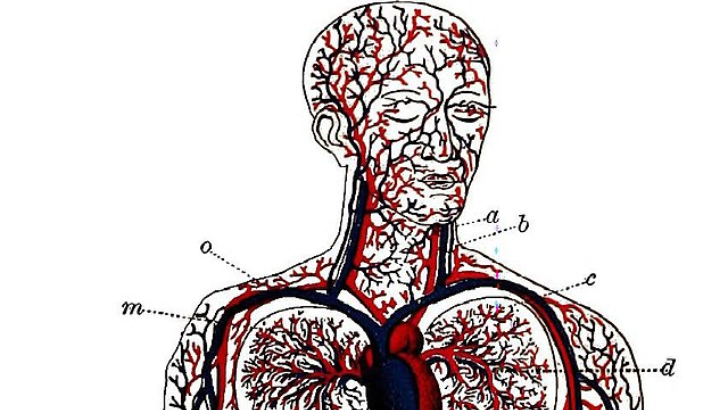

Why is it important to move blood through the body?

To deliver nutrients and oxygen throughout the body

To carry hormones around the body

All of the above

With good circulation, the white blood cells in your immune system will be transported around the body as needed. You’ll keep your organs in its best working order. Efficient circulation helps remove waste from the body created by different organs.

The term ______ refers to one-way “doors” that maintain blood flow in the proper direction.

Valves

The aortic, tricuspid, pulmonary, and mitral valves are the four valves that open and close in time with your heart’s pumping action. Only one direction of blood flow is necessary for your heart to function correctly. That is made possible by the “in” and “out” valves in your heart, which have flaps to seal or open the valve.

Your heart is divided into how many chambers?

4

The right and left atria are the heart’s upper chambers. The heart also has two lower chambers (the right and left ventricles). The left side of your heart receives oxygen-rich blood from the lungs and sends it through the aorta to the rest of your body. The right side of your heart pumps oxygen-poor blood to your lungs.

Through _______, blood travels from the lungs back to the heart.

Pulmonary veins

The pulmonary veins carry blood from your lungs that is rich in oxygen to your heart.